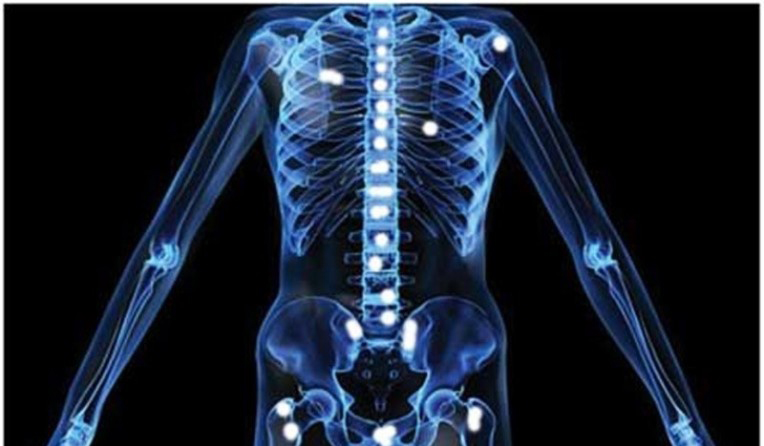

3. 뼈 고통

뼈 고통은 엉덩이나 허리와 같이 전립선에 가깝게 위치해 있는 곳의 뼈에 통증을 호소하게 됩니다. 전립선암은 주로 척추 뼈, 어깨뼈, 골반 뼈, 늑골 등에 많이 전이가 발생하고 골절이 발생할 가능성이 있다. 신경통과 위에서 해당하는 뼈 고통으로 동일한 증상이 나타내기도 하므로 디스크 환자가 아니어도 허리에 고통이 생길 수 있으며, 이로 인하여 일상생활에 불편함을 느끼게 됩니다.

뼈나 관절 시스템의 고통이 항상 전립선암을 나타내는 것은 아니긴 그렇지만 경계해야 할 초기 증상 중 하나인데요. 전립선암은 종종 전립선 근처 조직인 골반 림프절, 척추, 골반 뼈로 전이됩니다. 때로 허리나 엉덩이, 전립선에 가까운 부위에 고통을 느끼면서도 단순 신경통이나 관절통으로 넘기는 사람도 있습니다. 그러므로 이러한 부위에 설명할 수 없는 고통이 나타났다면 전문의의 진료를 받아보는 것이 중요해요.